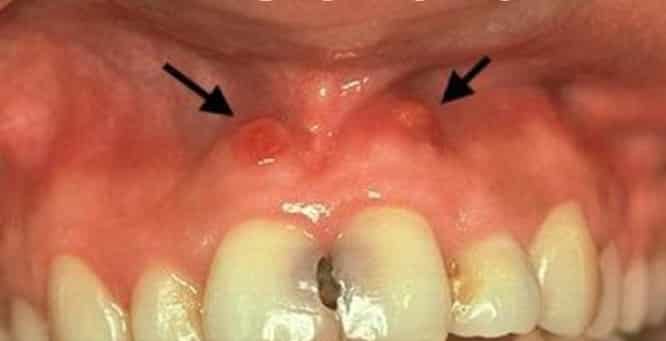

Киста — это образование у верхушки корня зуба, которое может возникнуть из-за неполного лечения пульпита или некачественного пломбирования каналов. Киста представляет собой капсулу, заполненную гноем, размеры которой могут варьироваться от 5 мм до 2-3 см. В некоторых случаях, когда киста переполняется гноем, она может образовать свищ на десне, сопровождающийся отёчностью, покраснением и увеличением размеров десны.

Если свищ находится в стадии образования, то есть присутствуют боль, отёк, покраснение, десна наливается гноем, повышается температура, то применяется вскрытие свищевого канала. Предварительно делается рентгеновский снимок, позволяющий установить наличие гранулёмы, кисты, незаполненных внутренних полостей в пульпе зуба. В процессе лечения необходимо обеспечить отток экссудата от гранулёмы (если она присутствует), удалить кисту и перепломбировать зуб.